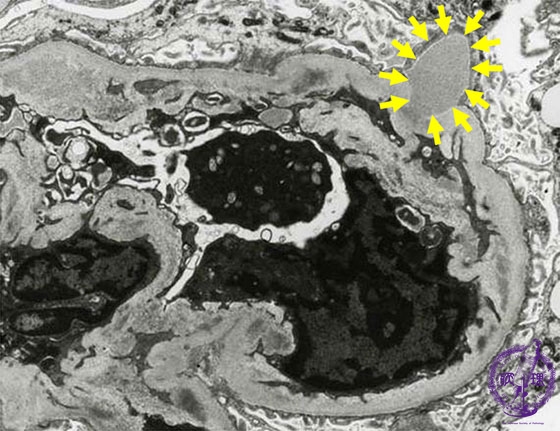

- (8)Endocapillary proliferative glomerulonephritis

Microscopic findings(electron microscopy): There are electron dense subepithelial deposits (yellow arrows). The deposits, known as humps, protrude predominantly from the subendothelial aspect.